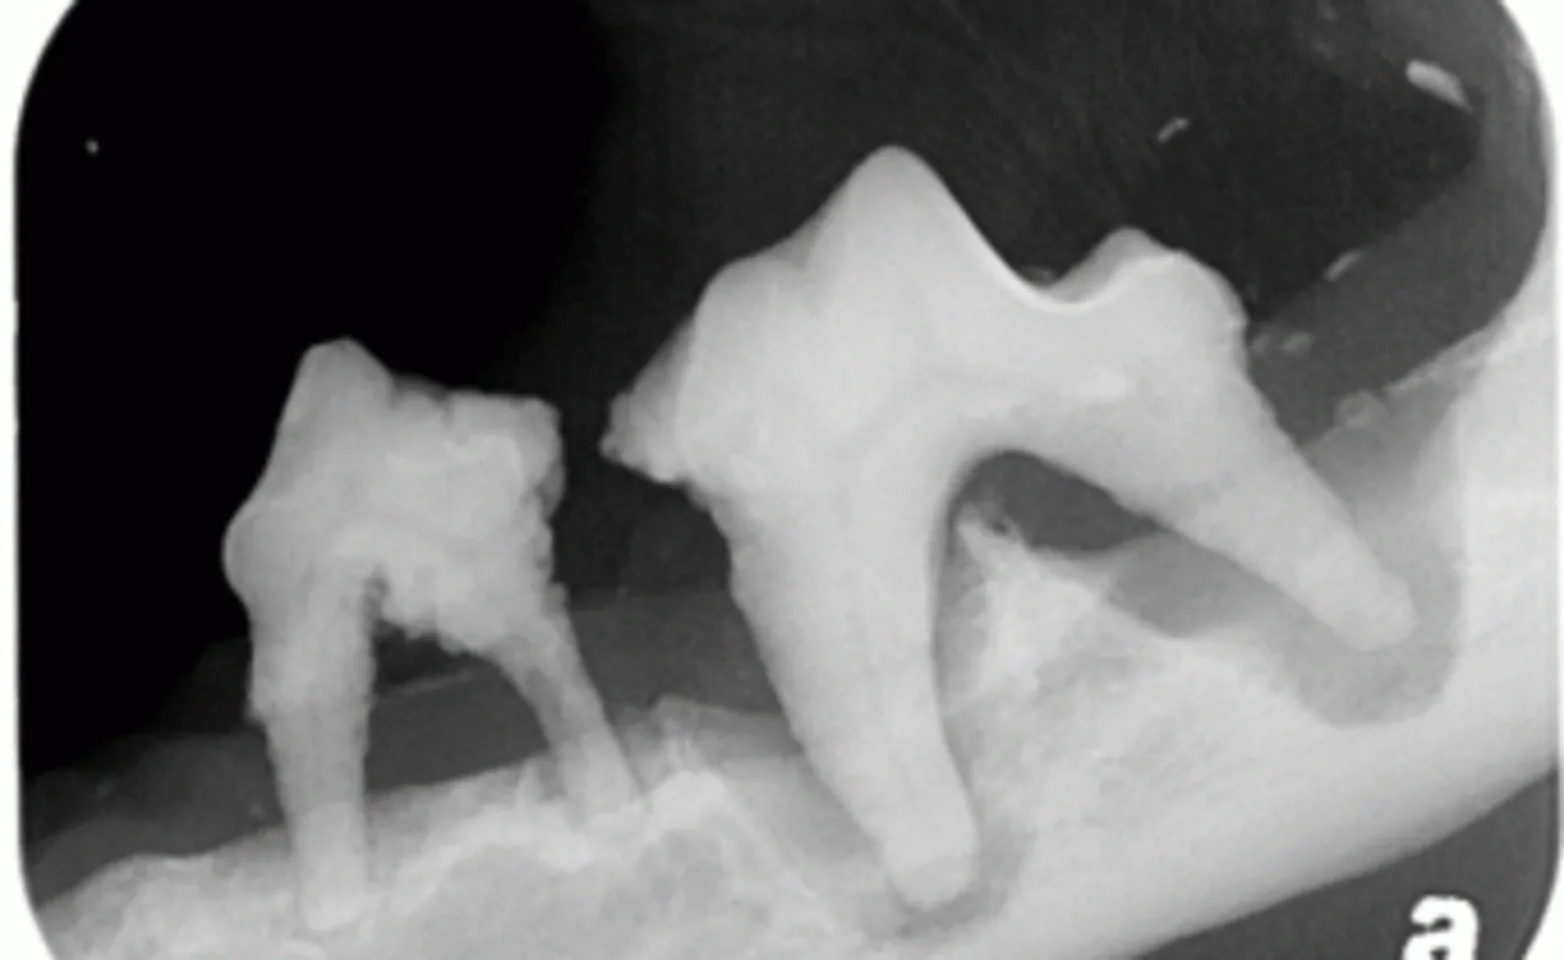

The above digital dental x-ray shows abscessed tooth roots with minimal bone present. Without the use of x-rays in this pet, one would not be able to know that extreme caution must be used to prevent jaw fracture during extraction.